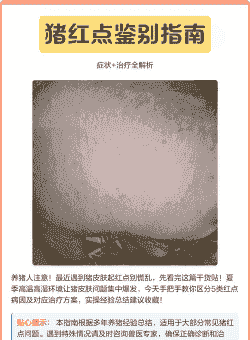

小猪全身发红可能是由以下几种疾病引起的:

由圆环病毒引起的多发生于12~14周龄仔猪的传染病,以皮肤出现红色丘疹为主,伴有厌食、呆滞、苍白、发热、结膜炎、呼吸困难、腹泻、消瘦等症状。

一种免疫抑制性的皮肤性疾病,在夏季非常多见,表现为猪只体表的不同部位出现数量不等、大小不一的粉红色或红紫色斑点。